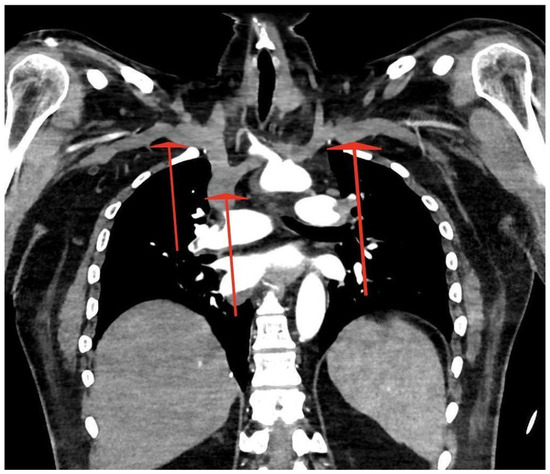

Massive Central Pulmonary Embolism with Riding Embolus and Concomitant Aortic Arch Embolism—Should We Diagnose Patients Earlier for Blood Clotting Disorders? Case Report

2. Case Report